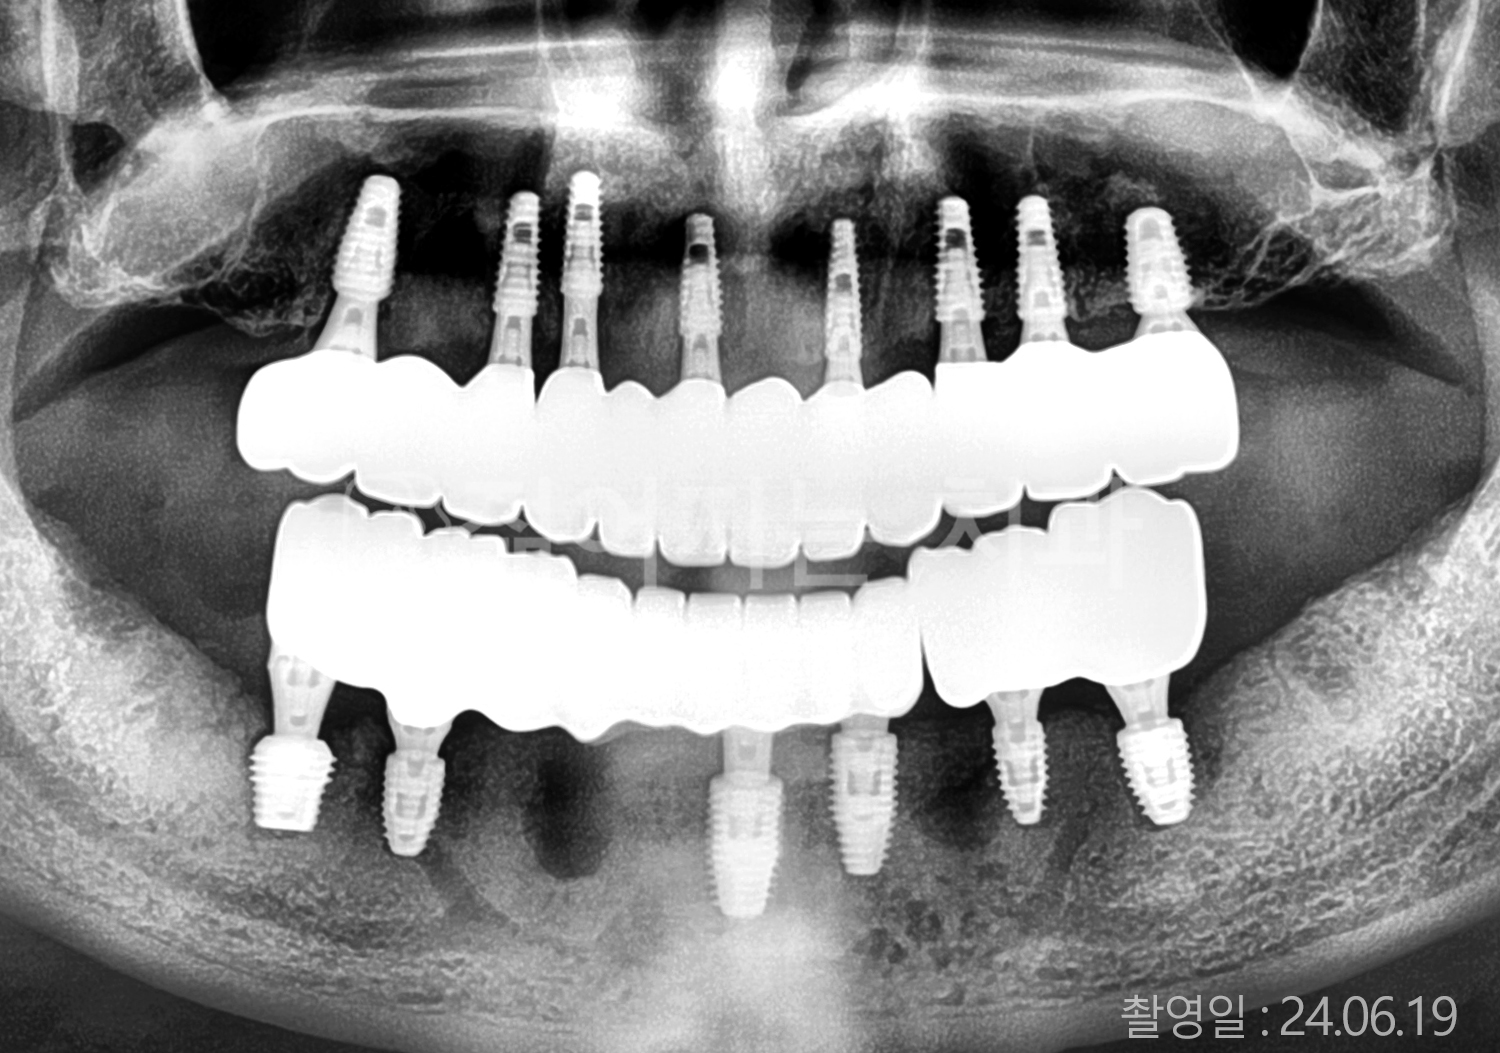

• 60대 고혈압, 당뇨, 고지혈증 전체치아 10개 이상 임플란트

• 60대 당뇨 전체치아 10개 이상 임플란트

• 70대 고혈압, 당뇨 전체치아 10개 이상 임플란트